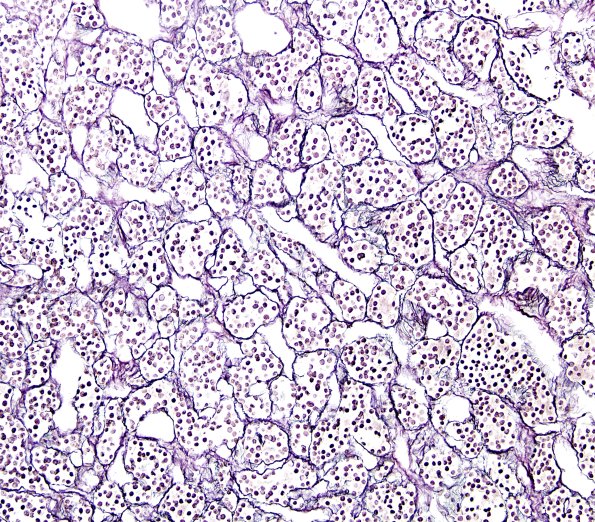

Washington University Experience | NORMAL | Pituitary gland | 4A2 Pituitary, normal gland retic 1

The cells in the normal pituitary adenohypophysis are typically arranged in small acini which are well shown in this reticulin stain. (retic)